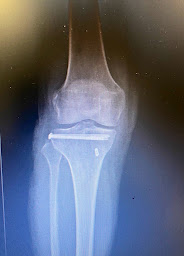

"Bonjour J ai été opéré il y a six mois par le Dr Hourtal. J ai apprécié son approche pendant les visites qui ont précedé mon opération (prothese totale du genou), la clarté de ses explications et je me suis senti en confiance. Très bon contact. Operation très bien passée avec une équipe au top ( gabin,anesthesiste et équipe infirmirers). Je sors aujourd'hui d une visite six mois après l opération. Discours toujours aussi rassurant et professionnel. Vraiment ravi de nos echanges et du resultat."

"Dr houtarl,je vous remercie pour cette opération que vous avez effectué le 27. 02 2025prothése au genou, qui c'est très bien passé.Monsieur hourtal et très compétent à l'écoute de très bons conseils, ainsi que son collègue Gabin,et anesthésiste Mr claverie qui m'ont très bien accueilli.,. maintenant rééducation à fond, pour que je puisse remonter sur la piste de danse 🙂😎pas danse avec les stars c'est pour les vieux !!!!😉☺️ à très bientôt......"